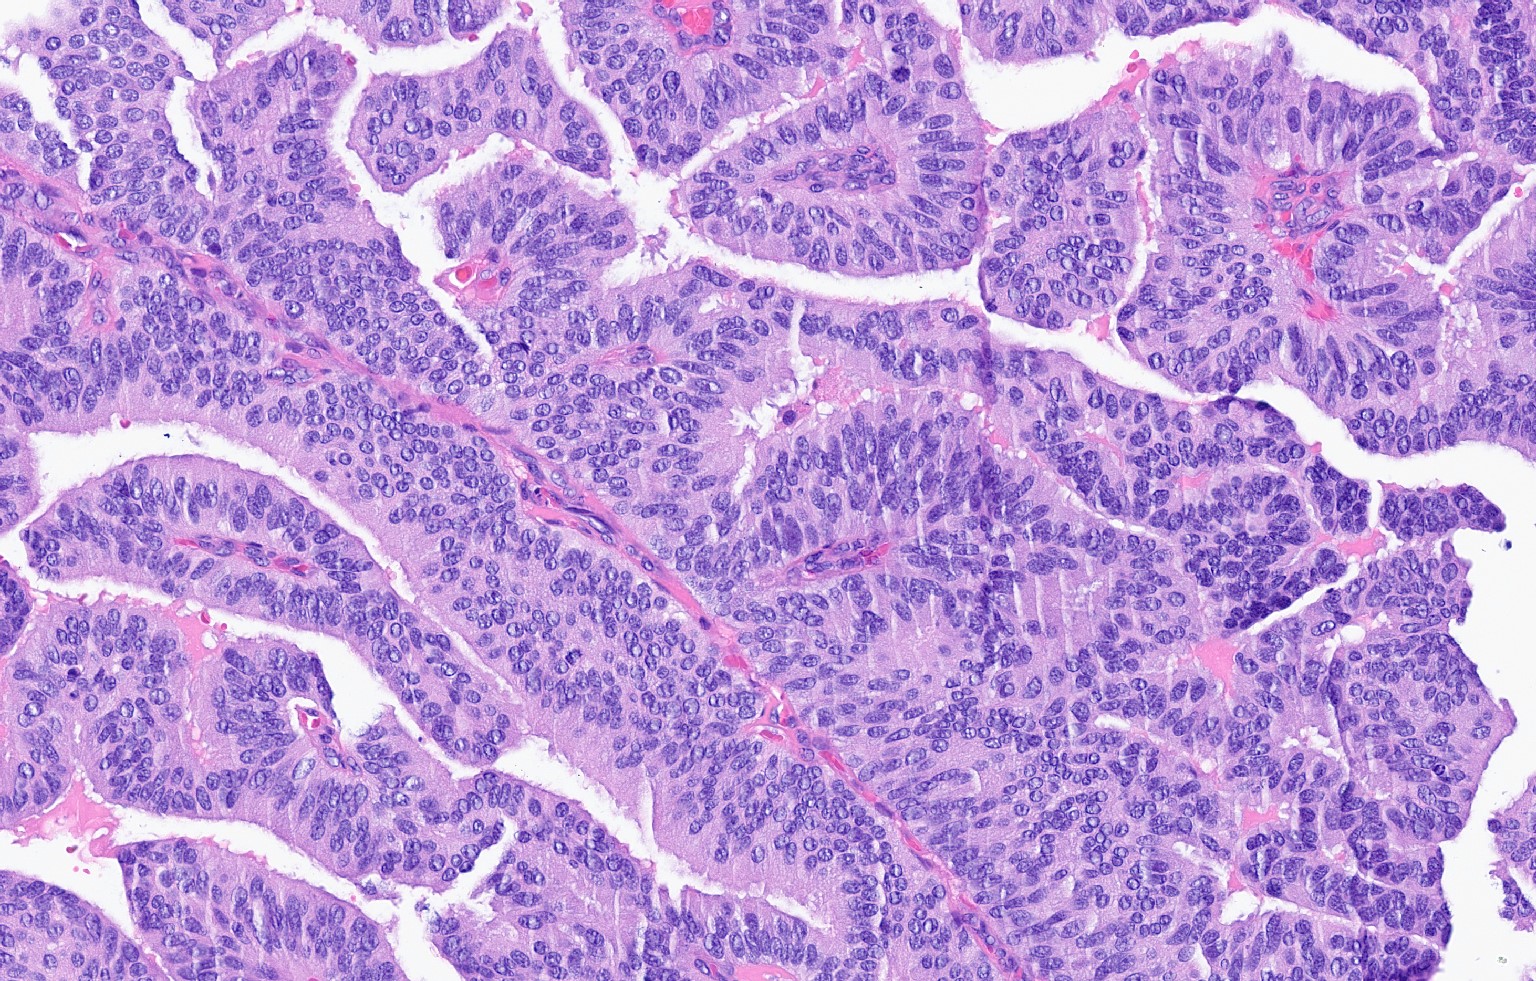

- Papillary tumor with pushing borders, may be within a cystically dilated duct, surrounded by a thick fibrous capsule (Histopathology 2008;52:20, Mod Pathol 2021;34:1044, Virchows Arch 2022;480:5)

- Delicate papillary fronds with fibrovascular cores lined by cuboidal to columnar epithelial cells with low to intermediate grade atypia

- Cribriform and solid architecture may be present

- Low mitotic activity (average 3 mitoses per 10 high power fields [HPFs]) (Am J Surg Pathol 2011;35:1)

- Most show complete lack of myoepithelial cells along the papillae and around the periphery of the tumor (Am J Surg Pathol 2006;30:1002, Am J Surg Pathol 2011;35:1)

- Basement membrane markers (collagen IV, laminin) may be expressed around the periphery (Pathobiology 2021;88:359, Am J Clin Pathol 2009;131:228)

Microscopic (histologic) images

Contributed by Kristen E. Muller, D.O. , Mariel Molina Nunez, M.D. and Julie Jorns, M.D. (Case #518)